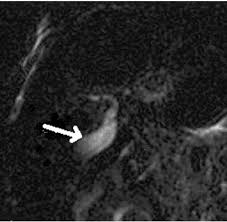

Hepatocellular cholestasis results from impairment of bile formation and indicates defective functioning of most or all hepatocytes. Biliary atresia imaging accessed 26 october 2017) fetal / embryonic form: Unequivocal evidence of intestinal excretion of radiolabel confirms patency of the extrahepatic biliary system. Congenital absence of biliary tree us: Biliary atresia is a serious liver disorder that occurs before or shortly after birth when a baby's bile ducts (the tubes that carry bile from the liver) become blocked. Gallbladder length less than 19 mm is suggestive for atretic gallbladder 2. Purpose to evaluate the incremental value of a combination of magnetic resonance cholangiopancreatography (mrcp) and ultrasonography (us), compared to us alone, for diagnosing biliary atresia (ba) in neonates and young infants with cholestasis. It is the most common cause of.

The us and mrcp studies were both performed on 64 neonates and. Purpose to evaluate the incremental value of a combination of magnetic resonance cholangiopancreatography (mrcp) and ultrasonography (us), compared to us alone, for diagnosing biliary atresia (ba) in neonates and young infants with cholestasis. We read with interest the article titled biliary atresia: Symptoms start shortly after birth; Hepatocellular cholestasis results from impairment of bile formation and indicates defective functioning of most or all hepatocytes. It is one of the most common causes of neonatal cholestasis, often causing cirrhosis immediately and leading to death and accounts for over half of children who undergo liver transplantation. Biliary atresia imaging accessed 26 october 2017) fetal / embryonic form: General discussion biliary atresia is a rare gastrointestinal disorder characterized by destruction or absence of all or a portion of the bile duct that lies outside the liver (extrahepatic bile duct). Once the liver fails, a liver transplant is required. Neonatal cholestasis has a variety of underlying causes. Embryologically each bile duct begins as a single layer of cells that surrounds a portal vein. Imaging in biliary atresia tuesday, october 26, 2004 biliary atresia a condition in which there is aplasia or obliteration of some or all of the extrahepatic biliary tree: Practice essentials biliary atresia (ba) is characterized by obliteration or discontinuity of the extrahepatic biliary system, resulting in obstruction of bile flow.